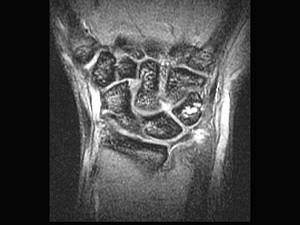

问题 男,27 岁,外伤后尺腕部疼痛,结合图像,最可能的诊断是 ( )

选项 A、尺骨骨折 B、三角纤维软骨复合体裂伤 C、三角骨无菌性坏死 D、三角骨骨折 E、未见异常

答案 B